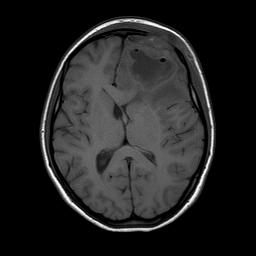

Dopo 10 giorni Martina ripete RMN di controllo (Figura 3) che documenta una marcata riduzione della lesione (diametro 35 x 24 x 18 mm) e una lieve diminuzione dell�edema perilesionale.

Figura 3. Lesione in sede frontale ipointensa nelle sequenze T1 pesate, di diametro 35 x 24 x 18 mm, circondato da cercine caratterizzato da marcato enhancement. Nelle sequenze T2 il cercine perilesionale appare ipointenso (a causa della presenza di collagene, emorragia e radicali liberi paramagnetici). Quadro complessivamente ridotto rispetto ai controlli precedenti. Ridotto l�effetto massa sul sistema ventricolare omolaterale.